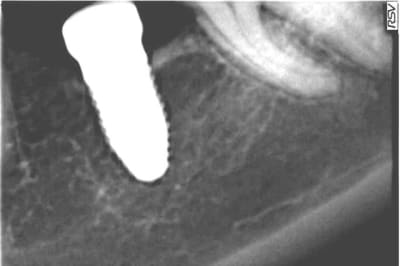

Je vous joins un cas qui m'a été adressé il y a deux ans à peu près pour une cratérisation (double). J'ai juste observé, d'autant que je n'étais pas le poseur. La radiographie de cette année était identique. La patiente n'a aucune symptomatologie. Je continue à surveiller.

PS : à noter également l'image au niveau du sinus. Pas d'évolution également depuis deux ans. La patiente m'a raconté avoir ressenti un "pic" lors de la pose.

Dommage Digit que ta radio ne soit pas dans le plan des spires.

sinon ta radio confirme mes propos

J'ai les radios préop et post op.

La rétro n'est vraiment pas terrible, mais depuis juin ça a quand même sacrément évolué.

Qu'en pensez-vous?

> AVANT

> APRES

> De mai à novembre

tu as perdu 1 ou 2 spires, vu la qualité de la première radio, difficile à dire.

La seconde radio est très contrastée par rapport à la première.